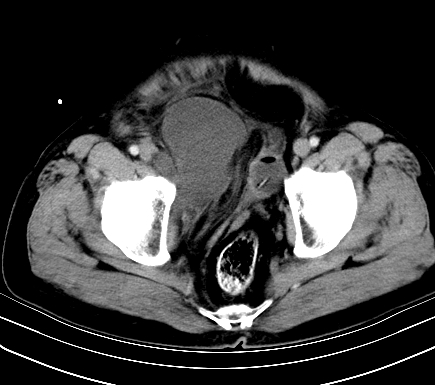

增强扫描

静脉期

延时期

【ct表现】

1、肿块巨大,往往位于腹膜后,长大后才引起症状而就诊;那么位于腹膜后的肿瘤80%为恶性肿瘤。

2、实性肿瘤,增强扫描轻度不均强化,实性肿瘤一般不是好东西。

3、肿瘤边缘似见少许脂肪样密度。

4、腹膜后未见肿大淋巴结,但肿瘤于临近的肠管及组织接触紧密。

【诊断】

腹部占位,考虑位于腹膜后的恶性肿瘤,脂肪肉瘤(实体型)可能性大。

【分析】

1、腹膜后的肿瘤少见,但种类繁多,包括脂肪肉瘤、纤维组织细胞肉瘤、纤维肉瘤、平滑肌肉瘤、恶性畸胎瘤、神经肉瘤、神经母细胞瘤、血管肉瘤及横纹肌肉瘤等,其中脂肪肉瘤为较常见的一种肿瘤。

2、增强扫描强化不明显,除脂肪肉瘤以外,一般肿瘤强化中度以上。脂肪肉瘤可不强化或轻度强化。

术后病理结果:腹膜后脂肪肉瘤。